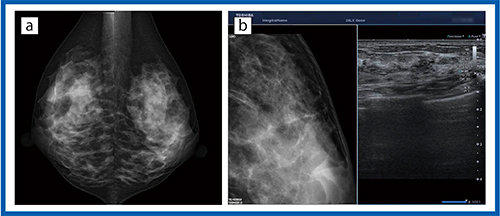

●症例6:石灰化症例

乳がんの4割程度は石灰化を呈するが,超音波画像で検出するのは難しい。

図6 aでは,左乳房に微小な円形の石灰化が見られるが,マンモグラフィ上このような石灰化を検出した場合,エコーで部位,低エコー域を観察する。東芝メディカルシステムズ社の超音波診断装置には,モニタ上に超音波画像とマンモグラフィ画像を並列表示して,石灰化などの検出を行いやすくする“リファレンス表示”が搭載されている(図6 b)。腺腔の中の点状エコーがAplio i800/i900の高画質化により明瞭に描出されているが,マンモグラフィ画像で確認しながら観察でき,診断精度の向上につながると期待される。

図6 症例6:石灰化症例

a:マンモグラフィ画像 b:リファレンス表示